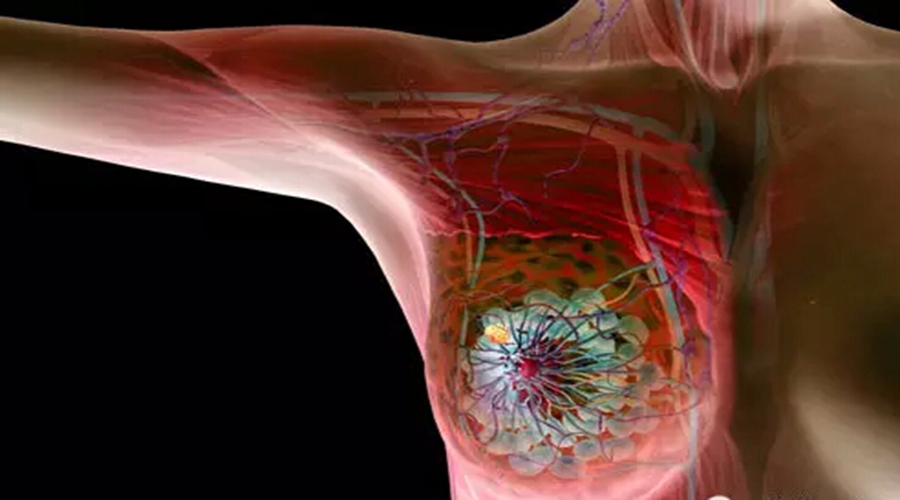

“在乳腺癌里面,三阴乳腺癌是极为棘手难以治疗的一种,通常病人能活过5年的很少,但她竟然与癌共存了15年,这真是肿瘤界的一个大奇迹!”刚得知郭女士的消息,圣丹福·广州圣丹福(肿瘤)医院许多肿瘤专家都表示十分震惊,如此评价道。

听马来西亚的朋友介绍,中国有比较新颖的治疗方法。很快,郭女士便来到了圣丹福·广州圣丹福(肿瘤)医院。而此时,郭女士的肝部肿瘤已经长到14cm大小,右上腹疼痛,走路像挺着一个大肚子。经医院的详细检查,郭女士被进一步确诊为三阴乳腺癌,伴随肝、肺转移。

三阴乳腺癌特指雌激素受体、孕激素受体及人表皮生长因子-2均呈阴性的乳腺癌患者。此类乳腺癌多见于年轻患者,愈后效果差,5年生存率不到15%。然而通过郭女士的例子,圣丹福·广州圣丹福(肿瘤)医院的肿瘤专家给广大患者提出了以下三点建议:首先,癌症患者是可以做到带瘤生存的;其次,得了三阴乳腺癌千万不要放弃,一定要有信心找到正确的医院接受对症的治疗方法;此外,鉴于目前乳腺癌的5年生存率高于50%,其他类型的乳癌患者更应该把握好治疗机会,实现早日康复。